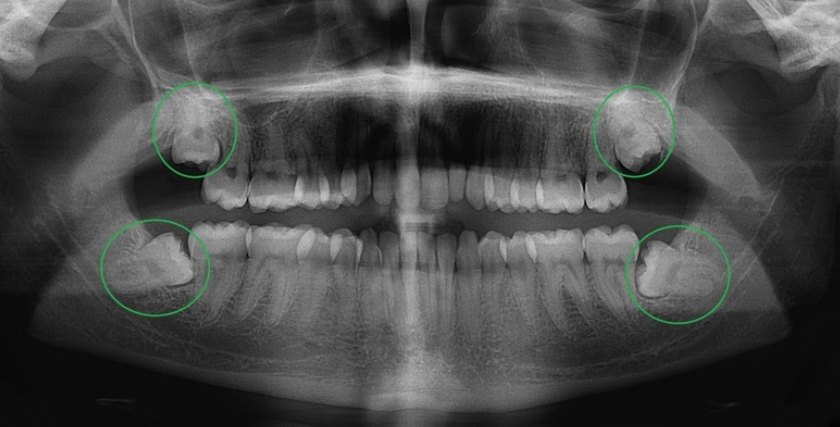

Hình ảnh chân răng khôn

Hình ảnh chân răng khôn được xác định rõ ràng nhất thông qua phim X-quang nha khoa. Việc chụp X-quang giúp nha sĩ nhìn thấy cấu trúc răng khôn, số lượng chân, hướng mọc và mức độ ảnh hưởng của răng khôn đối với các răng khác.

Dưới đây là một số đặc điểm hình ảnh chân răng khôn thường gặp:

- Chân răng khôn mọc thẳng và có ít chân thường dễ nhổ hơn.

- Chân răng khôn mọc cong hoặc có nhiều chân sẽ gây khó khăn hơn khi nhổ bỏ.

- Một số trường hợp răng khôn có chân đâm ngang hoặc mọc chen vào răng số 7, có thể gây đau nhức hoặc làm xô lệch răng.

Bác sĩ tiến hành khám tổng quát và chụp X-quang CT Cone Beam 3D để xác định chính xác vị trí, hình dạng, hướng mọc và số lượng chân răng khôn, đồng thời đánh giá mức độ ảnh hưởng đến răng kế cận, dây thần kinh và cấu trúc xung quanh.